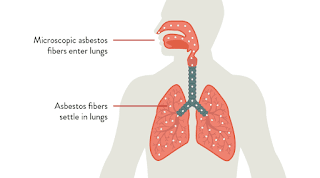

Η έκθεση σε αμίαντο μπορεί να οδηγήσει στην εμφάνιση προβλημάτων υγείας για όσους εκτίθενται στις ίνες του αμίαντου που υπάρχουν στον αέρα και οι οποίες μπορεί να εισέλθουν στον ανθρώπινο οργανισμό μέσω του αναπνευστικού και του πεπτικού συστήματος. Μέσω του δέρματος δεν γίνεται απορρόφηση. Ο αμίαντος γίνεται κίνδυνος για την υγεία όταν εισπνέονται ψηλές συγκεντρώσεις ινών για μεγάλο χρονικό διάστημα. Τα άτομα τα οποία εργάζονται καθημερινά με τον αμίαντο και εκτίθενται σ’ αυτόν συνεχώς μπορούν να υποστούν σοβαρές βλάβες στην υγεία τους.

Η αμιαντίαση είναι η πνευνοκονίωση που προκαλούν στους πνεύμονες οι ίνες του αμιάντου. Η αμιάντωση είναι μία ασθένεια που οφείλεται αποκλειστικά στις ίνες του αμίαντου και συχνά αποκαλείται ασθένεια της σκόνης. Όταν οι πολύ μικρές και λεπτές ίνες του αμίαντου εισπνέονται, ένας αριθμός απ’ αυτές διαπερνά τους φυσικούς μηχανισμούς καθαρισμού του εισπνεόμενου αέρα και καταλήγουν στις πνευμονικές κυψελίδες. Εκεί η παρουσία των ινών αυτών σηματοδοτεί μία αντίδραση με τον πνευμονικό ιστό. Ο συνήθως ελαστικός και μαλακός ιστός των πνευμόνων γίνεται σκληρός και ινώδης. Αυτό έχει σαν αποτέλεσμα σταδιακά το άτομο να παρουσιάζει δυσκολία στην αναπνοή. Είναι μια πολύ σοβαρή εκφυλιστική και προοδευτική ασθένεια των πνευμόνων που τους καταστρέφει σταδιακά.